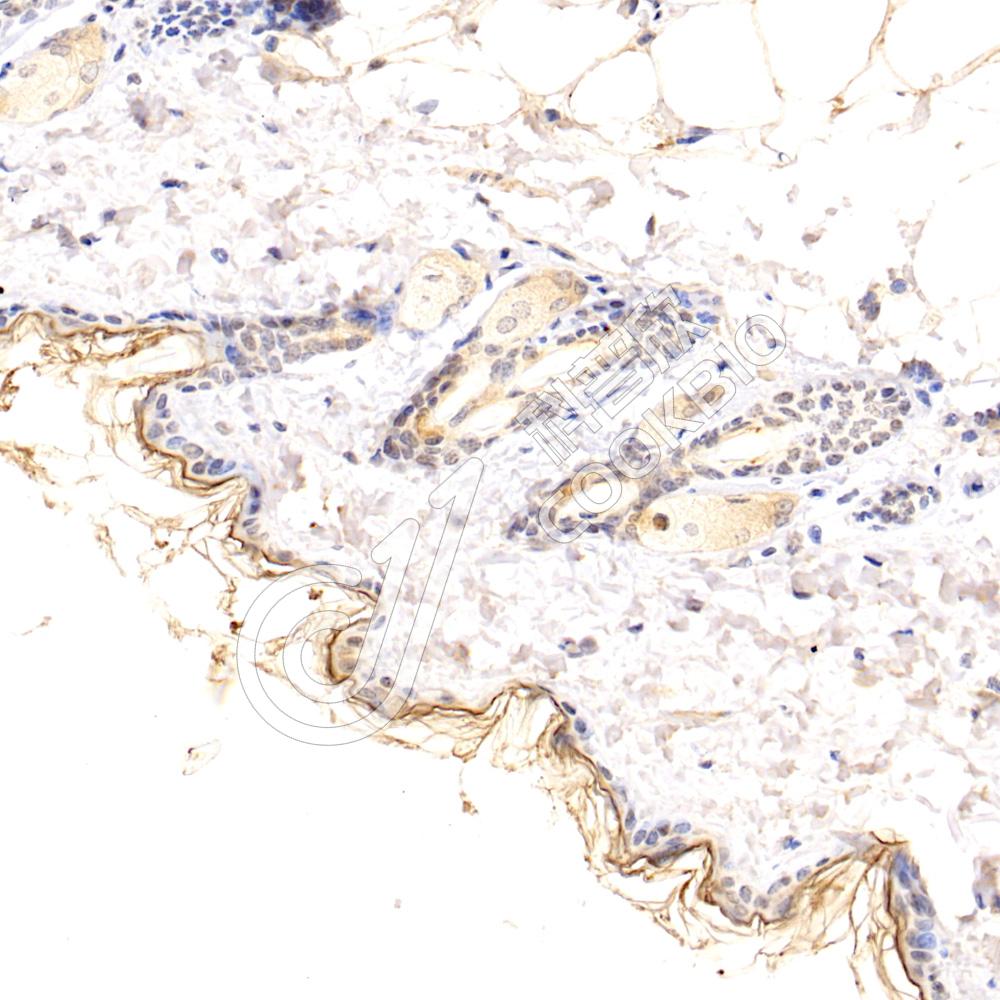

IHC检测Kallikrein 7/KLK7蛋白(货号 K1338961).

样品: 小鼠皮肤, 4%多聚甲醛 (货号KSG1101) 固定12-24小时.

抗原修复: 柠檬酸抗原修复液(干粉, pH 6.0) (KSG1201), 98℃, 20分钟.

—抗: 1: 1200稀释, 4℃ 孵育过夜.

二抗: S-vision免疫组化多聚二抗(山羊抗兔),即用型 (货号KB3906), 室温孵育20分钟.